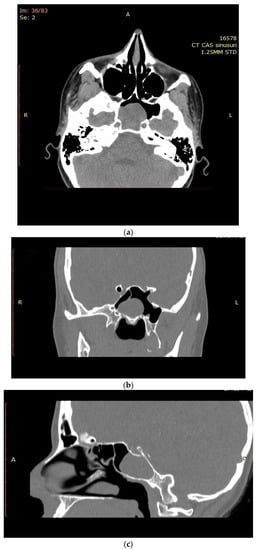

After surgery, clinical and endoscopic assessments were performed every month in the first three months, afterward the visits were scheduled for every three to six months. Flexible nasal endoscopy revealed patent nasal cavities and a patent left sphenoid sinus ostium (Figure 5). No signs of bleeding or abnormal nasal discharge were visible during any of the check-ups. Moreover, the patients’ quality of life improved due to tactical removal of the deviated nasal septum and turbinoplasty. Postoperatively, the patient declared the absence of headaches and improved nasal breathing. Four months after resection, the patient received an enhanced brain (head) magnetic resonance imaging (MRI). The left sphenoid sinus was mass-free, without residual hemangioma (Figure 6).

Figure 6. Enhanced brain MRI (axial and coronal plane)—no lesion detected within the left sphenoid sinus four months postoperatively.